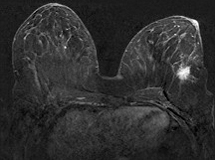

Mit der MR-Mammografie kann das Brustgewebe bis zur Brustwand und vorderen Achsel erfasst werden. Dabei werden die Brüste nicht komprimiert und verformt, was eine präzise Ortsbestimmung von Veränderungen in der Brust ermöglicht. Da das Brustgewebe in dünnen Schichten untersucht wird, ist die Diagnose nicht durch Überlagerungen beeinträchtigt. Während der Untersuchung wird über eine Nadel in einer Vene ein Kontrastmittel appliziert, wodurch die Durchblutung von Herdbefunden sichtbar gemacht wird. Dies ist für die Tumorerkennung von entscheidender Bedeutung. Bei vorhandenen Brustimplantaten können Defekte erkannt werden und die Region hinter den Implantaten beurteilt werden.

• ergänzend zur Mammografie und zur Mammasonografie, wenn diese Verfahren keine ausreichende Klärung der Frage nach Brustkrebs erreichen konnten,

• zur präoperativen Ausdehnungsdiagnostik, z.B. beim invasiv lobulären Mammakarzinom (ILC),

Für die Untersuchung werden zunächst Schnittbilder ohne Kontrastmittel angefertigt. Um die Lage und Unversehrtheit von vorhandenen Brustimplantaten zu überprüfen, werden spezielle Schichtführungen und Sequenzen verwendet. Anschließend wird das Kontrastmittel über die zuvor eingebrachte Nadel verabreicht und Schnittbilder nach Kontrastmittelgabe angefertigt. Insbesondere für die Erkennung von Brustkrebs ist der Einsatz von Kontrastmittel zwingend notwendig. Die gesamte Untersuchung dauert ca. 20 Minuten.